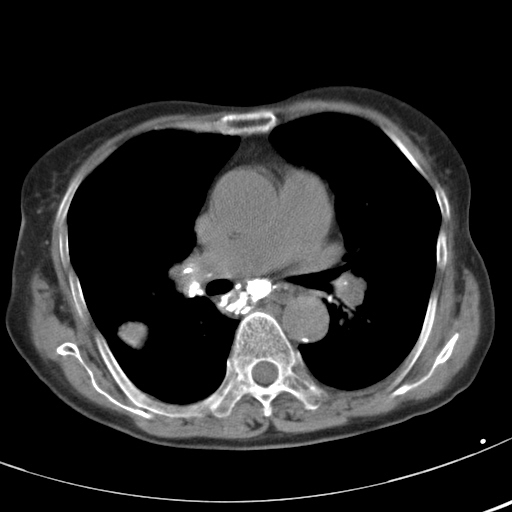

以下是引用hhcckk在2007-3-2 14:51:00的发言:[br]考虑结核球可能性大,依据[br]1病灶在下叶背段,结核的好发部位[br]2病灶内有大量的钙化,纵隔内有大量的淋巴结钙化[br]3重要的是半年前与现在相比无变化,假如是肿瘤的话不会这么‘善良’[br]4病灶周围卫星灶不明显,病灶有毛刺,胸膜凹陷,肿瘤不能完全排除,有条件的话最好做个活检

以下是引用liuyue在2007-3-2 17:15:00的发言:[br]1位置:右上叶后段[br]2性质:大分叶、粗长毛刺、条状斑片状钙化、纵隔多发淋巴结钙化,无强化,故考虑:肺结核灶(陈旧)